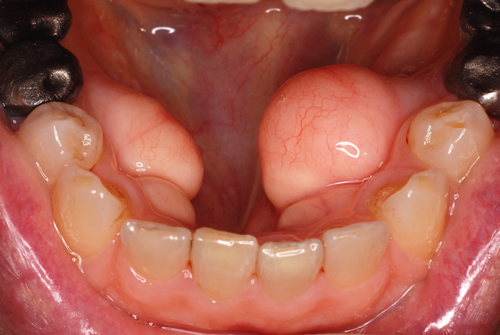

あまり自覚症状はないのでご本人が気づいていない場合も多いのですが、骨がコブのように大きくなったものを骨隆起といいます。原因はハッキリしていないようですが、経験的に咬む力が強い人に多いように思います。突然気がついて癌と思ってしまう方が時々いますが、全くそのような心配は要りません。

特に不自由が無ければ放置して良いのですが、歯を失って義歯を入れるときには邪魔になります。この写真のようにここまで大きくなると除去が必要になります。これは下顎ですが上顎では口蓋部に好発します。